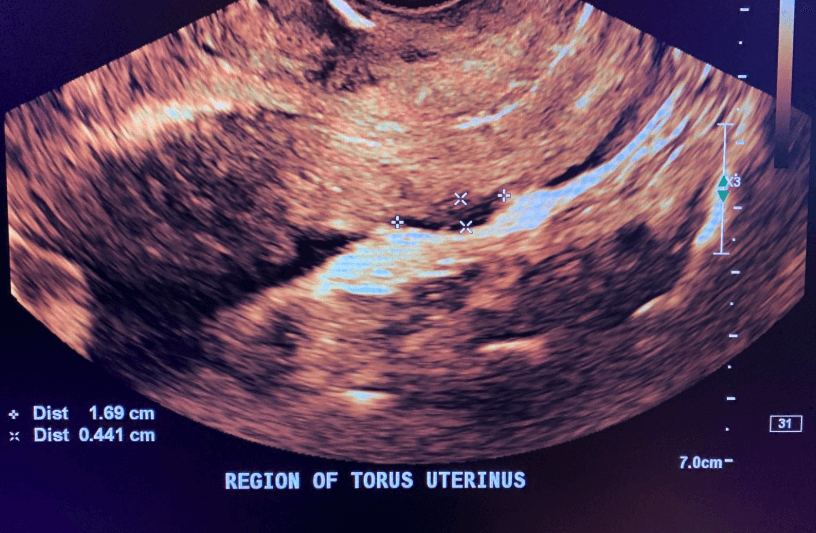

Endometriotic nodule in the pouch of Douglas

- Uterosacral ligament nodules

- Pouch of Douglas obliteration